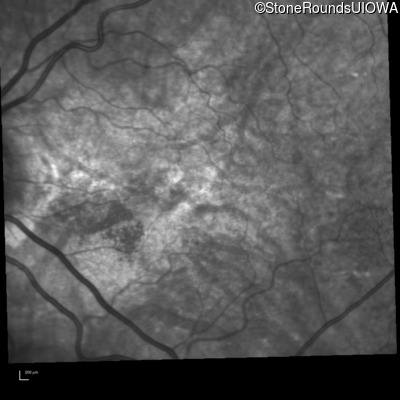

Infrared Fundus Photograph - Right - 20/30 +1

Exemplar